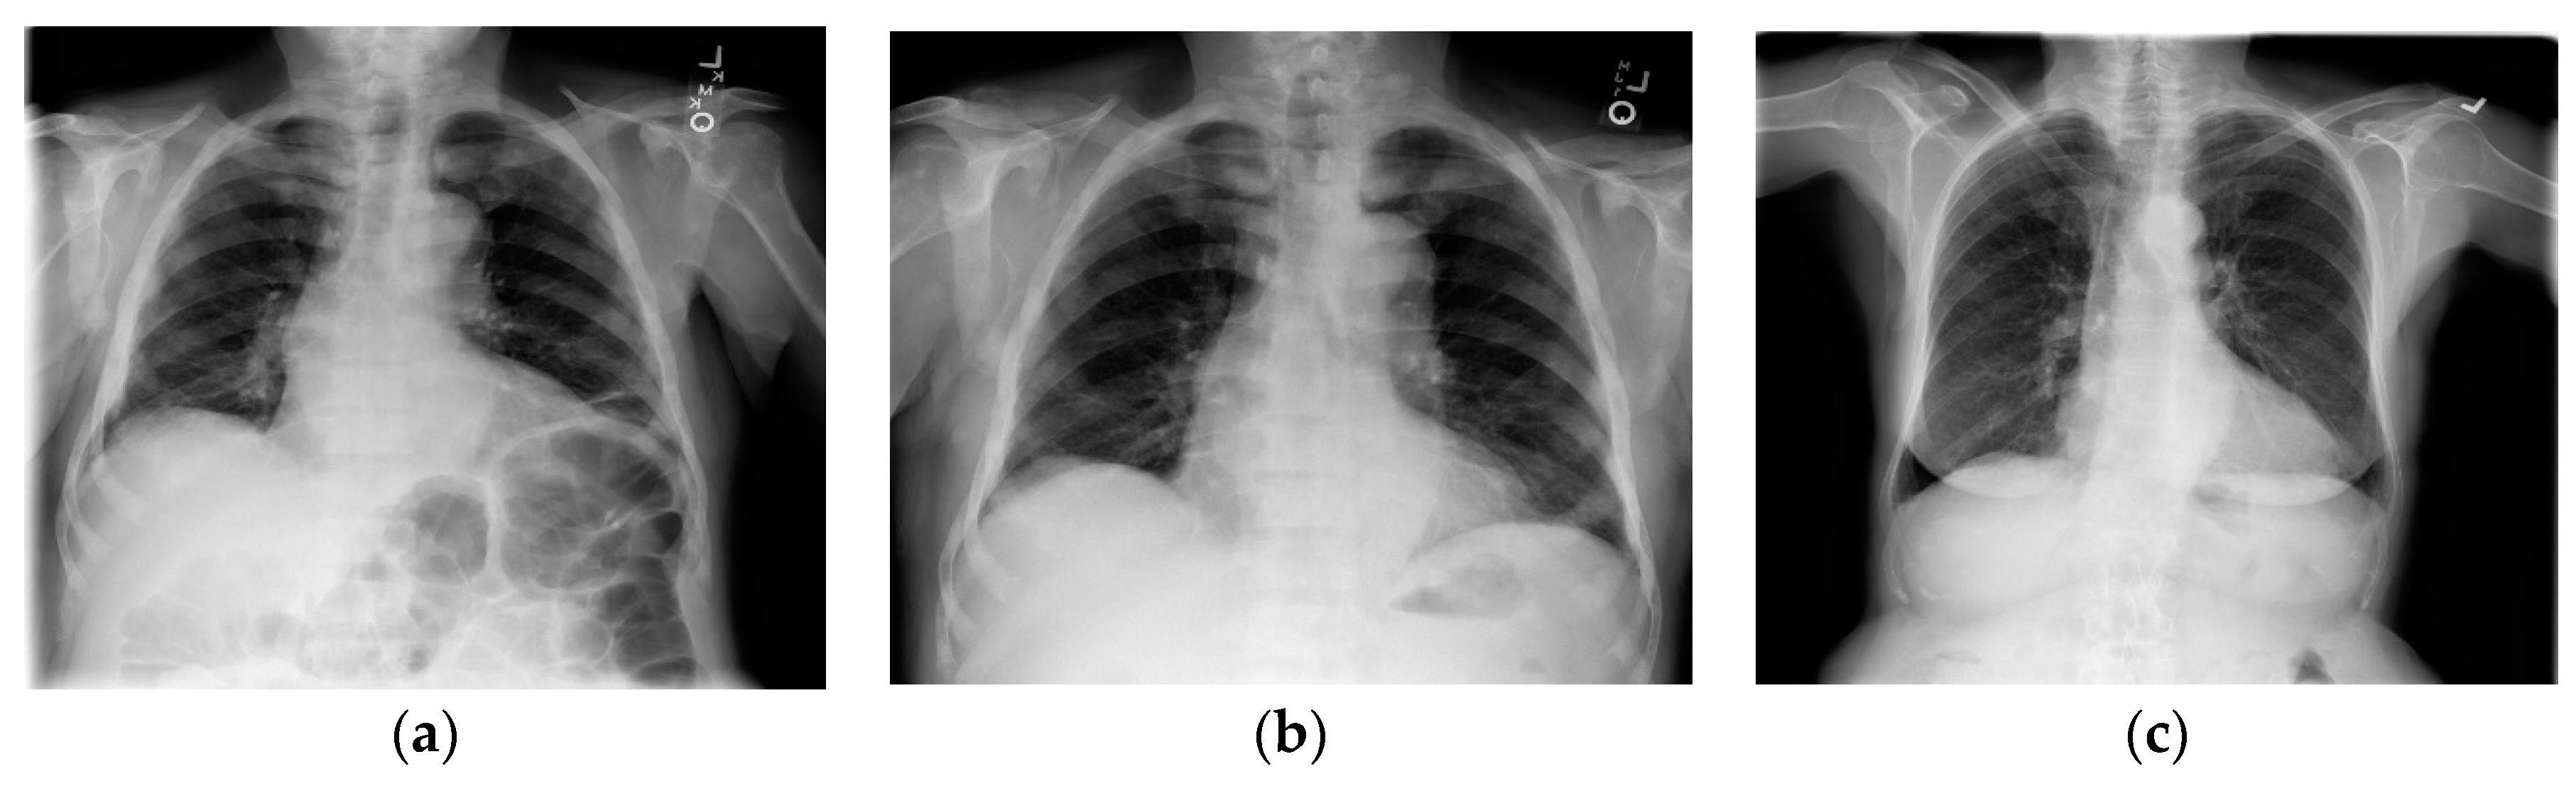

- Wang, X.; Peng, Y.; Lu, L.; Lu, Z.; Bagheri, M.; Summers, R.M. ChestX-Ray8: Hospital-scale Chest X-Ray database and benchmarks on weakly-supervised classification and localization of common thorax diseases. In Proceedings of the 2017 IEEE Conference on Computer Vision and Pattern Recognition (CVPR), Honolulu, HI, USA, 21–26 July 2017; pp. 3462–3471. [Google Scholar] [CrossRef]